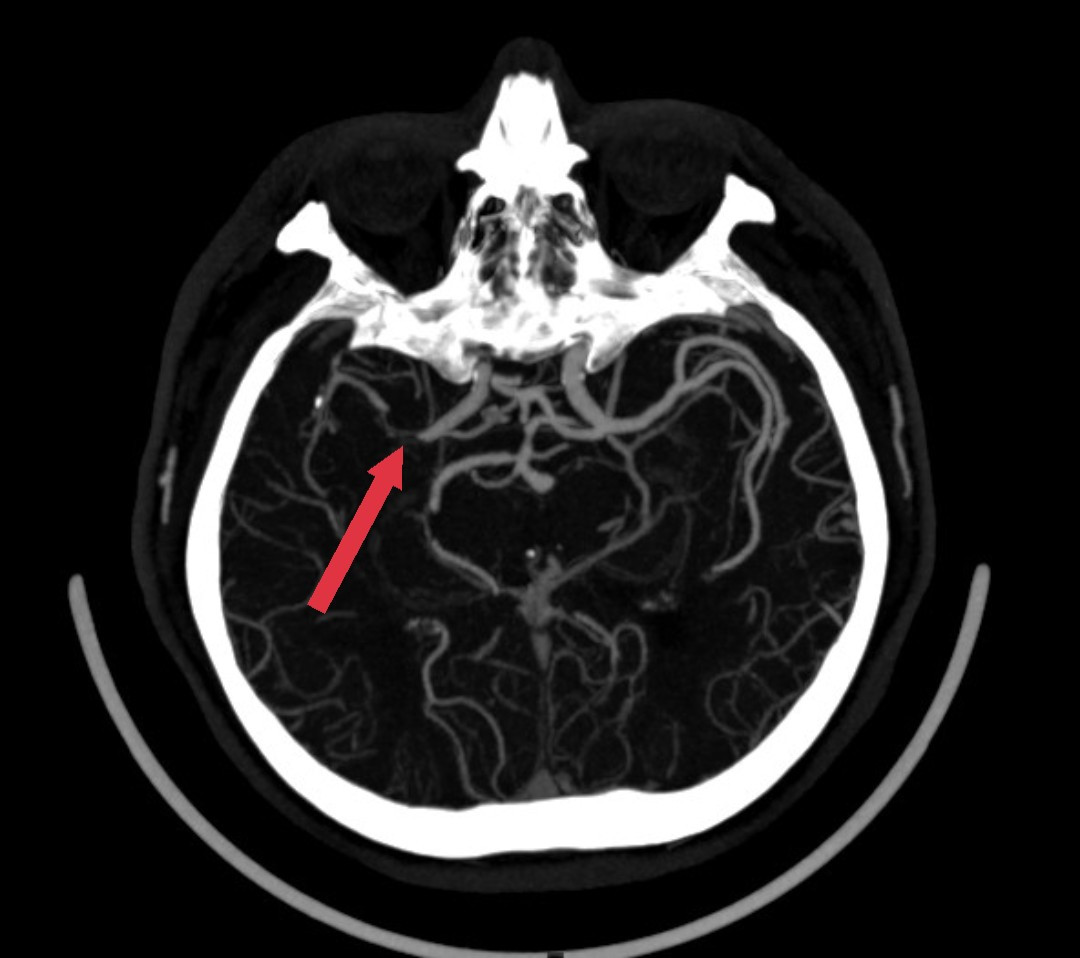

Các bác sĩ nhanh chóng chẩn đoán người bệnh bị đột quỵ nên quyết định kích hoạt khẩn cấp quy trình cấp cứu. Qua hình ảnh chụp cắt lớp vi tính sọ não, bác sĩ phát hiện người bệnh bị nhồi máu não cấp (mạch máu não bị tắc bởi cục máu đông).

| Một bên động mạch não của bệnh nhân bị tắc hoàn toàn thời điểm nhập viện cấp cứu |

Kết quả kiểm tra chuyên sâu hình ảnh chụp mạch máu não của bệnh nhân ghi nhận, ông S.D.J. bị hẹp nặng động mạch não giữa (đoạn M1). Theo bệnh sử, người đàn ông Hàn Quốc bị cao huyết áp nhưng ông không đi khám bệnh định kỳ.